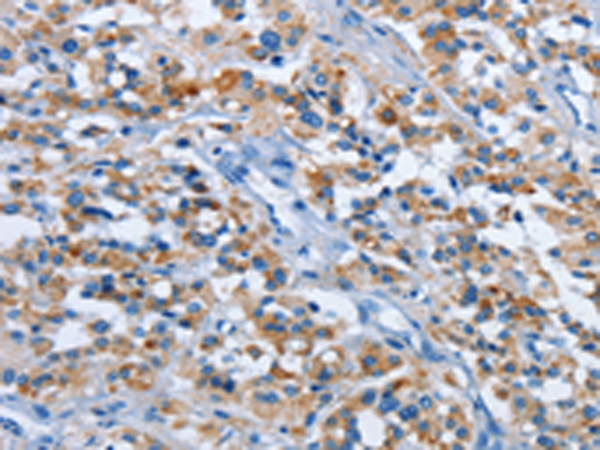

分类: 科研抗体货号: P08314别名: MLSTD1; SDR10E2应用: WB,IHC反应种属: Human, Mouse